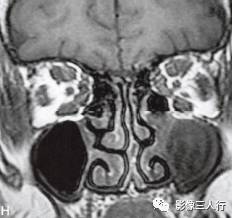

A~C.抑脂T2WI横断面;D~F.T1WI横断面;G~H.T1WI冠状面;I.抑脂T2WI冠状面

横断面显示双侧眼球明显突出,双侧眼球角膜至双侧颧突连线的垂直距离分别为:右侧2.2cm、左侧2.3cm。双侧眼外肌明显增粗,以双侧内、外、上、下直肌明显,短径均可达7mm,且以肌腹增粗明显呈梭形,T1WI等信号(图D~F,图G~H),抑脂T2WI呈明显高信号(图A~C,图I)。双侧眼眶内及球后脂肪增多,双侧眼球内侧至眼眶内侧壁的脂肪厚度增宽。双侧视神经形态及走行正常,双侧眼球晶体、玻璃体形态及信号正常。

影像学检查可帮助该病的诊断与鉴别诊断。CT表现为眼外肌增粗,主要为肌腹增粗,附着于眼球壁上的肌腱不增粗,少数也可同时累及眼外肌肌腹和肌腱。最常累及下直肌,其次为内直肌、上直肌和上提肌,偶尔累及外直肌。MRI表现为受累的眼外肌T1WI低信号,T2WI高信号,压脂T2WI为高信号;晚期眼外肌已纤维化,在T1WI和T2WI均呈低信号。增强扫描急性期时增粗的眼外肌有轻至中度强化,晚期眼外肌纤维化时则无强化。眶内脂肪体积增多表现为球周脂肪尤其是眶前部脂肪的增多。本例影像征象较典型。